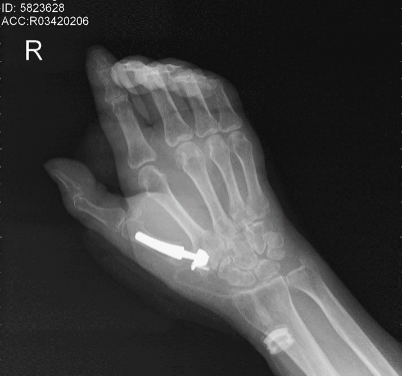

歷經(jīng)1個多小時的手術(shù),患者的右手第一腕掌關(guān)節(jié)被全新的人工假體所代替。術(shù)后拍攝x線檢查,假體擺放位置精確,與術(shù)前規(guī)劃完美匹配?;颊咝g(shù)后1個月來院復(fù)查時關(guān)節(jié)周圍無明顯紅腫,疼痛感較術(shù)前明顯改善,關(guān)節(jié)功能恢復(fù)正常水平。

△術(shù)后1個月患者右手第一掌指關(guān)節(jié)康復(fù)良好